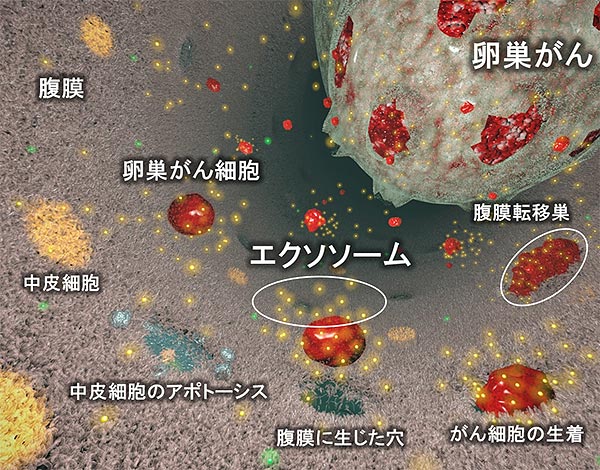

卵巣がんの治療を困難にする腹膜播種性転移のメカニズムを世界に先駆け